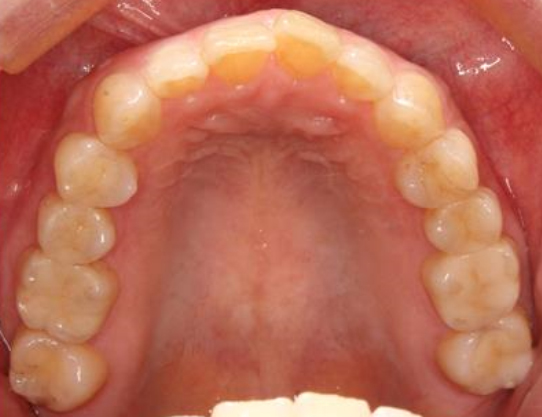

銀歯の詰め物・被せ物を、e-maxのインレーやクラウンに置き換えた症例。